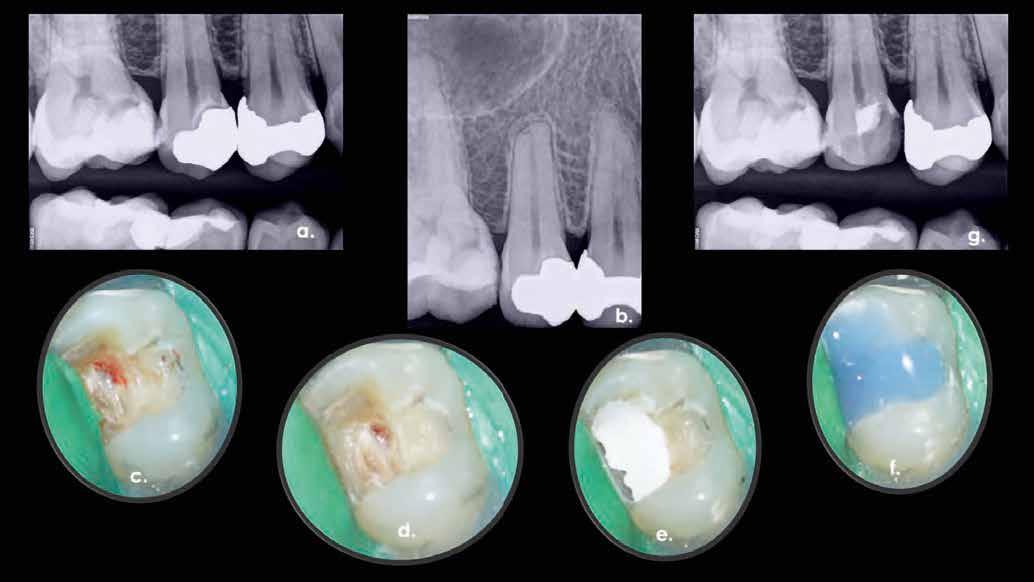

KOMPLEX FOGAZATI REHABILITÁCIÓ

A fogazat elhasználódása alatt azoknak a degeneratív folyamatoknak az összesített hatását értjük, melyeken az élet során a szervezet keresztülmegy. Ezek lehetnek a fogérintkezések közben fellépő mechanikai erők (abrázió, attríció), endogén vagy exogén eredetű savas közegek által kiváltott kémiai behatások (erózió), kariogén baktériumok által okozott pathológiás folyamatok és parodontális elváltozások, valamint iatrogén ártalmak.

A felnőtt páciensek kezelése során általában egyszerre több ellátásra szoruló elváltozást is diagnosztizálhatunk: hiányzó fogak, kopott fogazat, esetleg régi, nem megfelelő, sérült fogpótlások, rendellenes helyzetben lévő fogak stb… Ezen páciensek kezelésekkel kapcsolatos kérései mindig az esztétikai vagy a rágással kapcsolatos kívánságaik kielégítését szolgálja. A kezelések során a fogorvosoknak nem csak a páciensek kéréseinek teljesítésére, hanem ezzel egyidejűleg a fogazat általános megjelenésének és funkciójának lehetőség szerinti javítására is törekedniük kell. Mindemellett a lehető legtöbb saját foganyag megőrzését és az évek során elvesztett kemény- és lágyrészek pótlását (pl.: hiányzó fogak, sorvadt állcsontgerinc, lágyszöveti defektusok) is szem előtt kell tartaniuk, úgy, hogy közben egy hosszú távon fenntartható eredményekkel járó kezelési tervet állítanak össze. Ezek mindig összetett esetek. Annak érdekében, hogy a fentiekben megfogalmazott összes kezelési célt teljesíteni tudjuk, interdiszciplináris megközelítésre van szükség. Az ilyen komplex rehabilitációs kezeléseket „fogászati megfiatalításnak” nevezzük. Ezeknek a beavatkozásoknak lényege az elhasználódott fogazat biológiai szempontokat figyelembe vevő minimál invazív módon történő helyreállításában rejlik, mely folyamat végére a páciensek fogai visszanyerhetik fiatalkori megjelenésüket.

A rehabilitációs kezeléseknek a célja, hogy a páciensek a lehető leghosszabb időn keresztül képesek legyenek mosolyogni és rágni. A protetikai kezeléseket végző fogorvosoknak helyre kell tudni állítaniuk a fogívek szabályos lefutását és az alsó és felső fogív között megfelelő interokkluzális érintkezéseket kell létrehozniuk. Így lehet csak az ellátás befejezését követően elért végeredmény biológiai szempontokat figyelembe vevő esztétikáját, funkcionális megfelelőségét, hosszú távú fenntarthatóságát biztosítani.

Nagyon fontos, hogy már a kezelések elején meghatározzuk, hogy melyek azok a hiányzó fogak, amelyeket a későbbiekben pótolni szeretnénk, valamint helyesen diagnosztizáljuk a kariológiai, endodonciai vagy parodontológiai okok miatt ellátást igénylő elváltozásokat. Szintén kiemelt jelentőséggel bír a fogak megtarthatóságának kiértékelése. A kezelési terv felállítása során tisztában kell lennünk azzal, hogy mely fogak alkalmasak fogpótlások ideiglenes vagy végleges elhorgonyzására.

A preprotetikai fázisban el kell látnunk a diagnosztizálásra került kórfolyamatokat, megfelelő pozícióba kell állítanunk a megtartani kívánt fogakat, pótolnunk kell az elvesztett csontállományt, valamint gondoskodnunk kell az íny megfelelő állapotáról. Ha szükség van rá, úgy a foghiányok pótlására szolgáló dentális implantátumok is ebben a fázisban kerülnek behelyezésre. Általánosságban elmondható, hogy azokat a kezeléseket, amelyek befejezése biológiai okok miatt hosszú időt vesz igénybe (pl.: fogszabályozás, csontpótlás, implantáció), a lehető leghamarabb érdemes elkezdeni.

A fogszabályzó kezelések egyik legfontosabb célja, hogy elérjük a lehető legharmonikusabb interokkluzális fogérintkezéseket, továbbá az állcsont relációs helyzetének frontális és szaggitális síkban is megfelelőnek kell lennie. A fogszabályzás befejezésekor a fogpozícióknak nem orthodonciai, hanem protetikai szempontok szerint kell ideálisnak lenniük. Az Invisalign ClinCheck szoftver (Align Technology) segítségével a protetikus az orthodontussal együtt meg tudja határozni azokat a végső fogpozíciókat, amelyek a lehető legjobb végeredmény biztosításához elengedhetetlenek. Bizonyos klinikai paramétereket, mint a fogak klinikai koronájának nagyságát, az egyes fogak fogíven belüli optimális pozícióját, a fogívek egymáshoz viszonyított helyzetét, a fogak között látható rések nagyságát, a frontfogak tengelyének dőlését, az overjet és overbite mértékét már a kezelések megkezdése előtt pontosan definiálni kell. Ezeket az adatokat viszont csak a tervezett végleges fogpótlás ismeretében lehet meghatározni, ezért van szükség az orthodontus és a protetikus szoros együttműködésére.